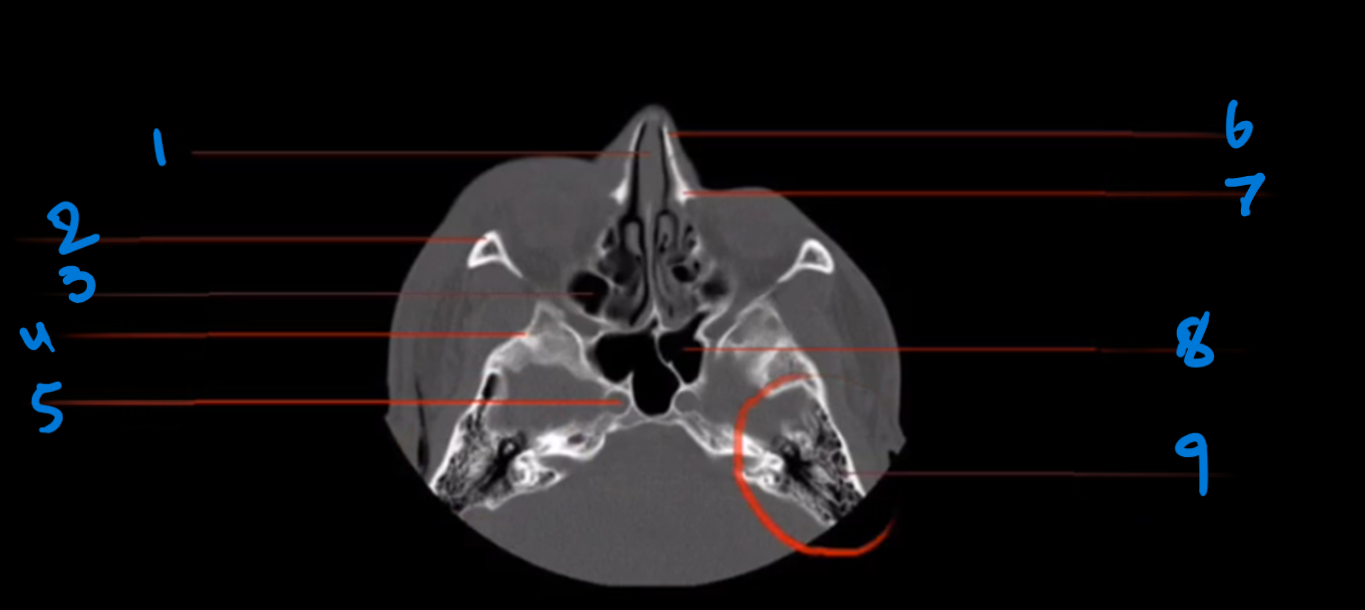

What is landmark #1 called?

Nasal bone

What is landmark #2 called?

Perpendicular plate, ethmoid bone

What is landmark # 3 called?

Zygoma

What is landmark # 4 called?

Sphenoid Sinus

What is landmark # 5 called?

Ethmoid air cells (sinus)

What is landmark # 6 called?

Sphenoid bone

What is landmark # 7 called?

Dorsum Sellae, sphenoid bone

What is landmark # 8 called?

Temporal Bone